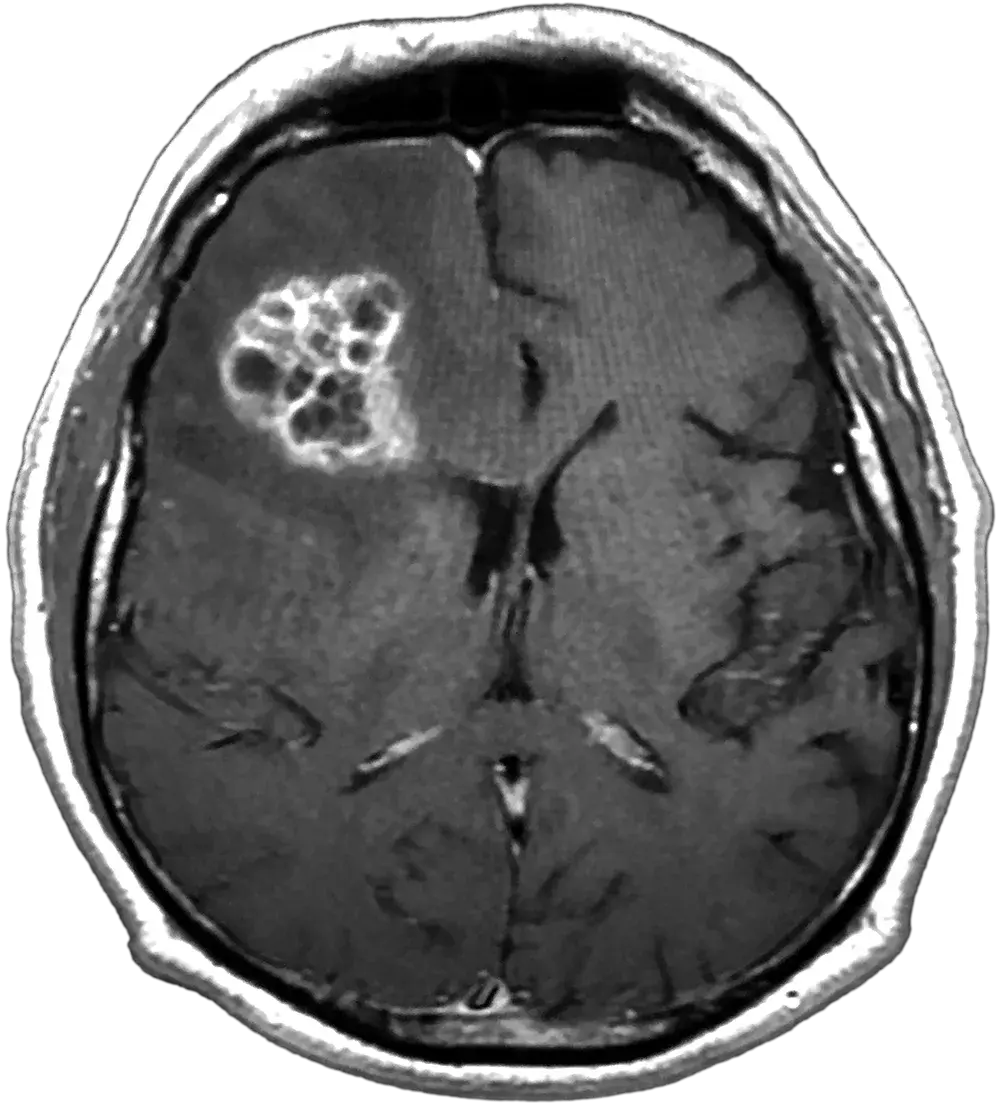

Clinical Presentation of GBM

GBM commonly presents in the cerebral hemispheres with 95% of tumors arising in the supratentorial region (cerebrum). Tumors are usually irregular shaped lesions, creating a typical histopathological pattern on Magnetic Resonance Imaging (MRI) and seen as an enhancing lesion.2,5